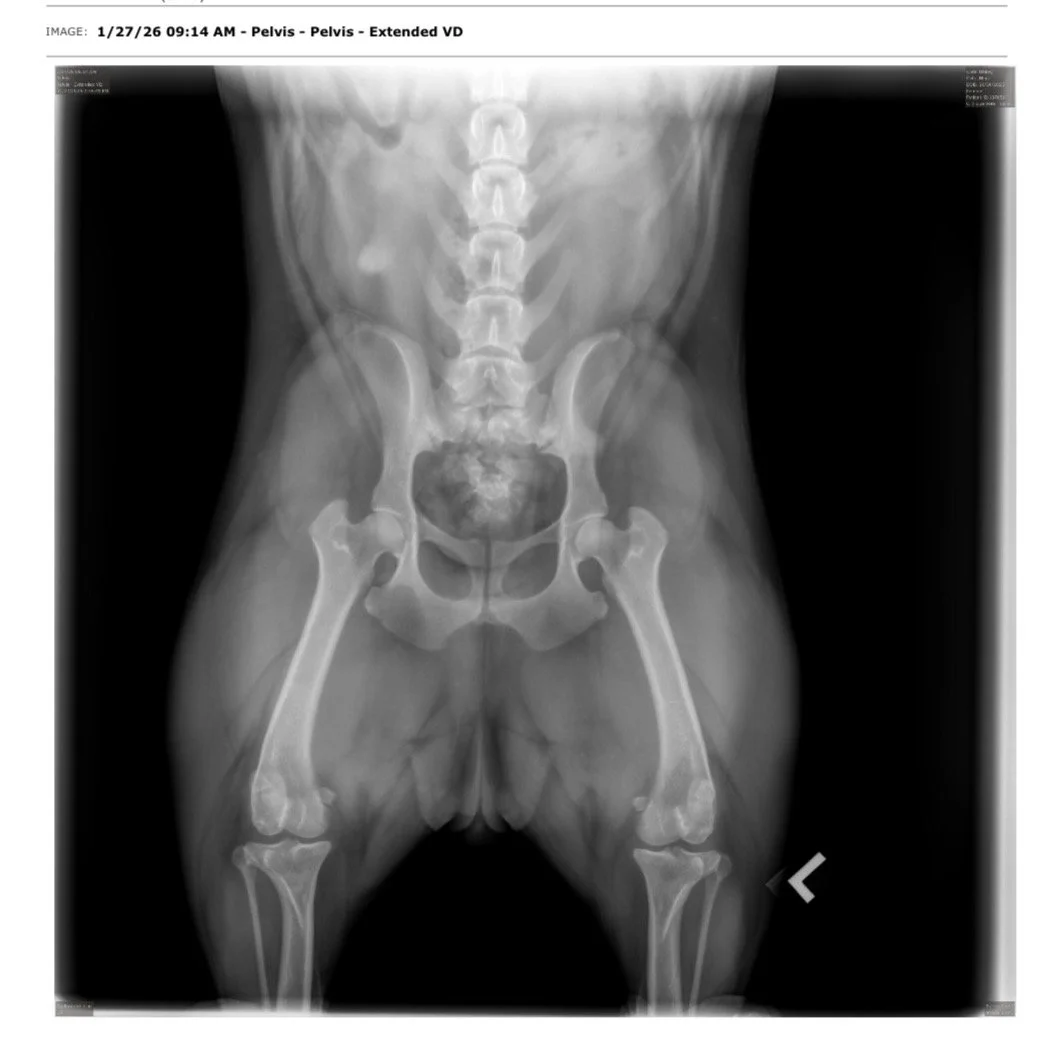

Testés OFA de la race pour Hanches, Coudes, Rotules, Colonne Vertébrale, Coeur & Yeux.